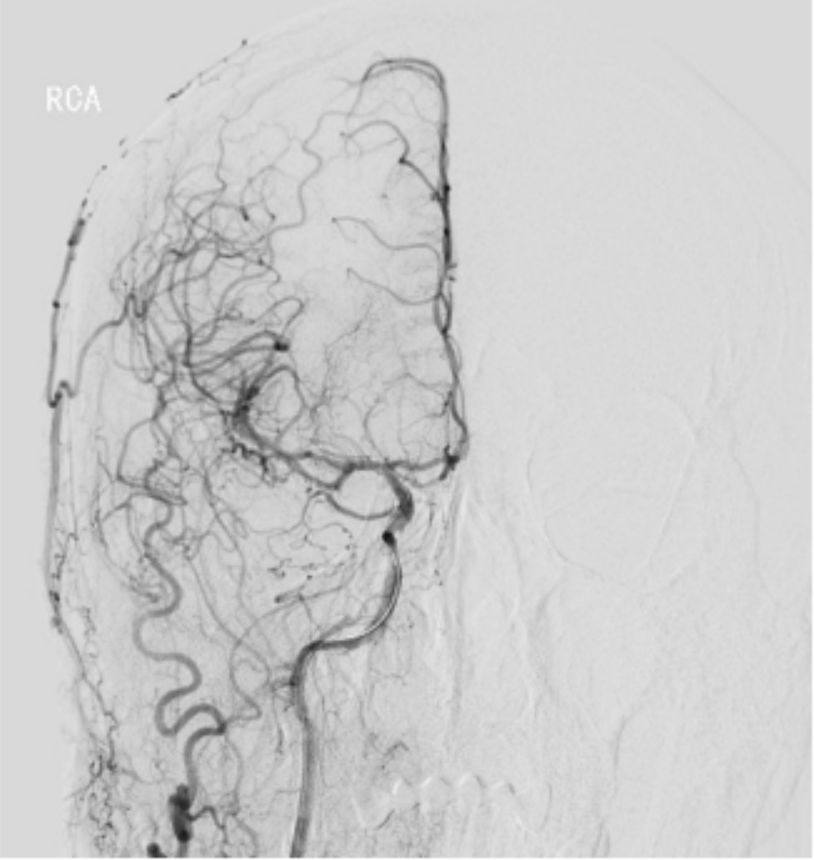

2019-06-07外院DSA:右侧颈内动脉闭塞(图2)。

图2